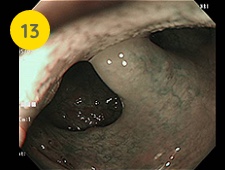

ハイビジョン内視鏡

食道がんの症例です。 早期の食道がんは内視鏡で治療できますので、定期的な内視鏡検査が重要です